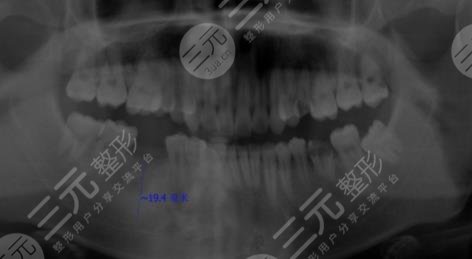

When I had a face-to-face consultation here, everything was relatively smooth, the doctor first took a film of my teeth, and then selected a more suitable dental implant according to my situation, I chose an imported dental implant, and in the process of implantation, I could feel that the doctors of Beijing Weir Dental Hospital were more professional, and there was no excessive pain during the operation, which was relatively comfortable.